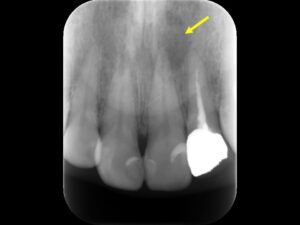

初診時レントゲン。他院にて根管治療を数か月行っているが痛みが続いていると訴えて来院。根管内には依然に詰めた薬がまだ残っているように見える。根尖部の骨破壊はほとんど認めない。